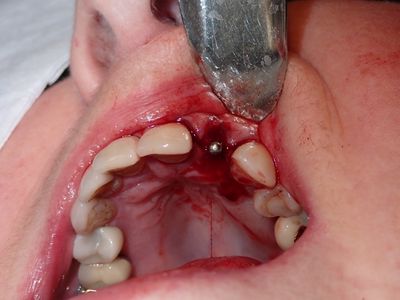

long root, atraumatic exo, loss of labial bone at apical end of socket, implant placed in ideal position, socket and buccal grafted with allograft and collagen membrane. Sutured prior to loading implant with screw-retained temp crown out of centric and protrusive occlusion

PA180027.JPG